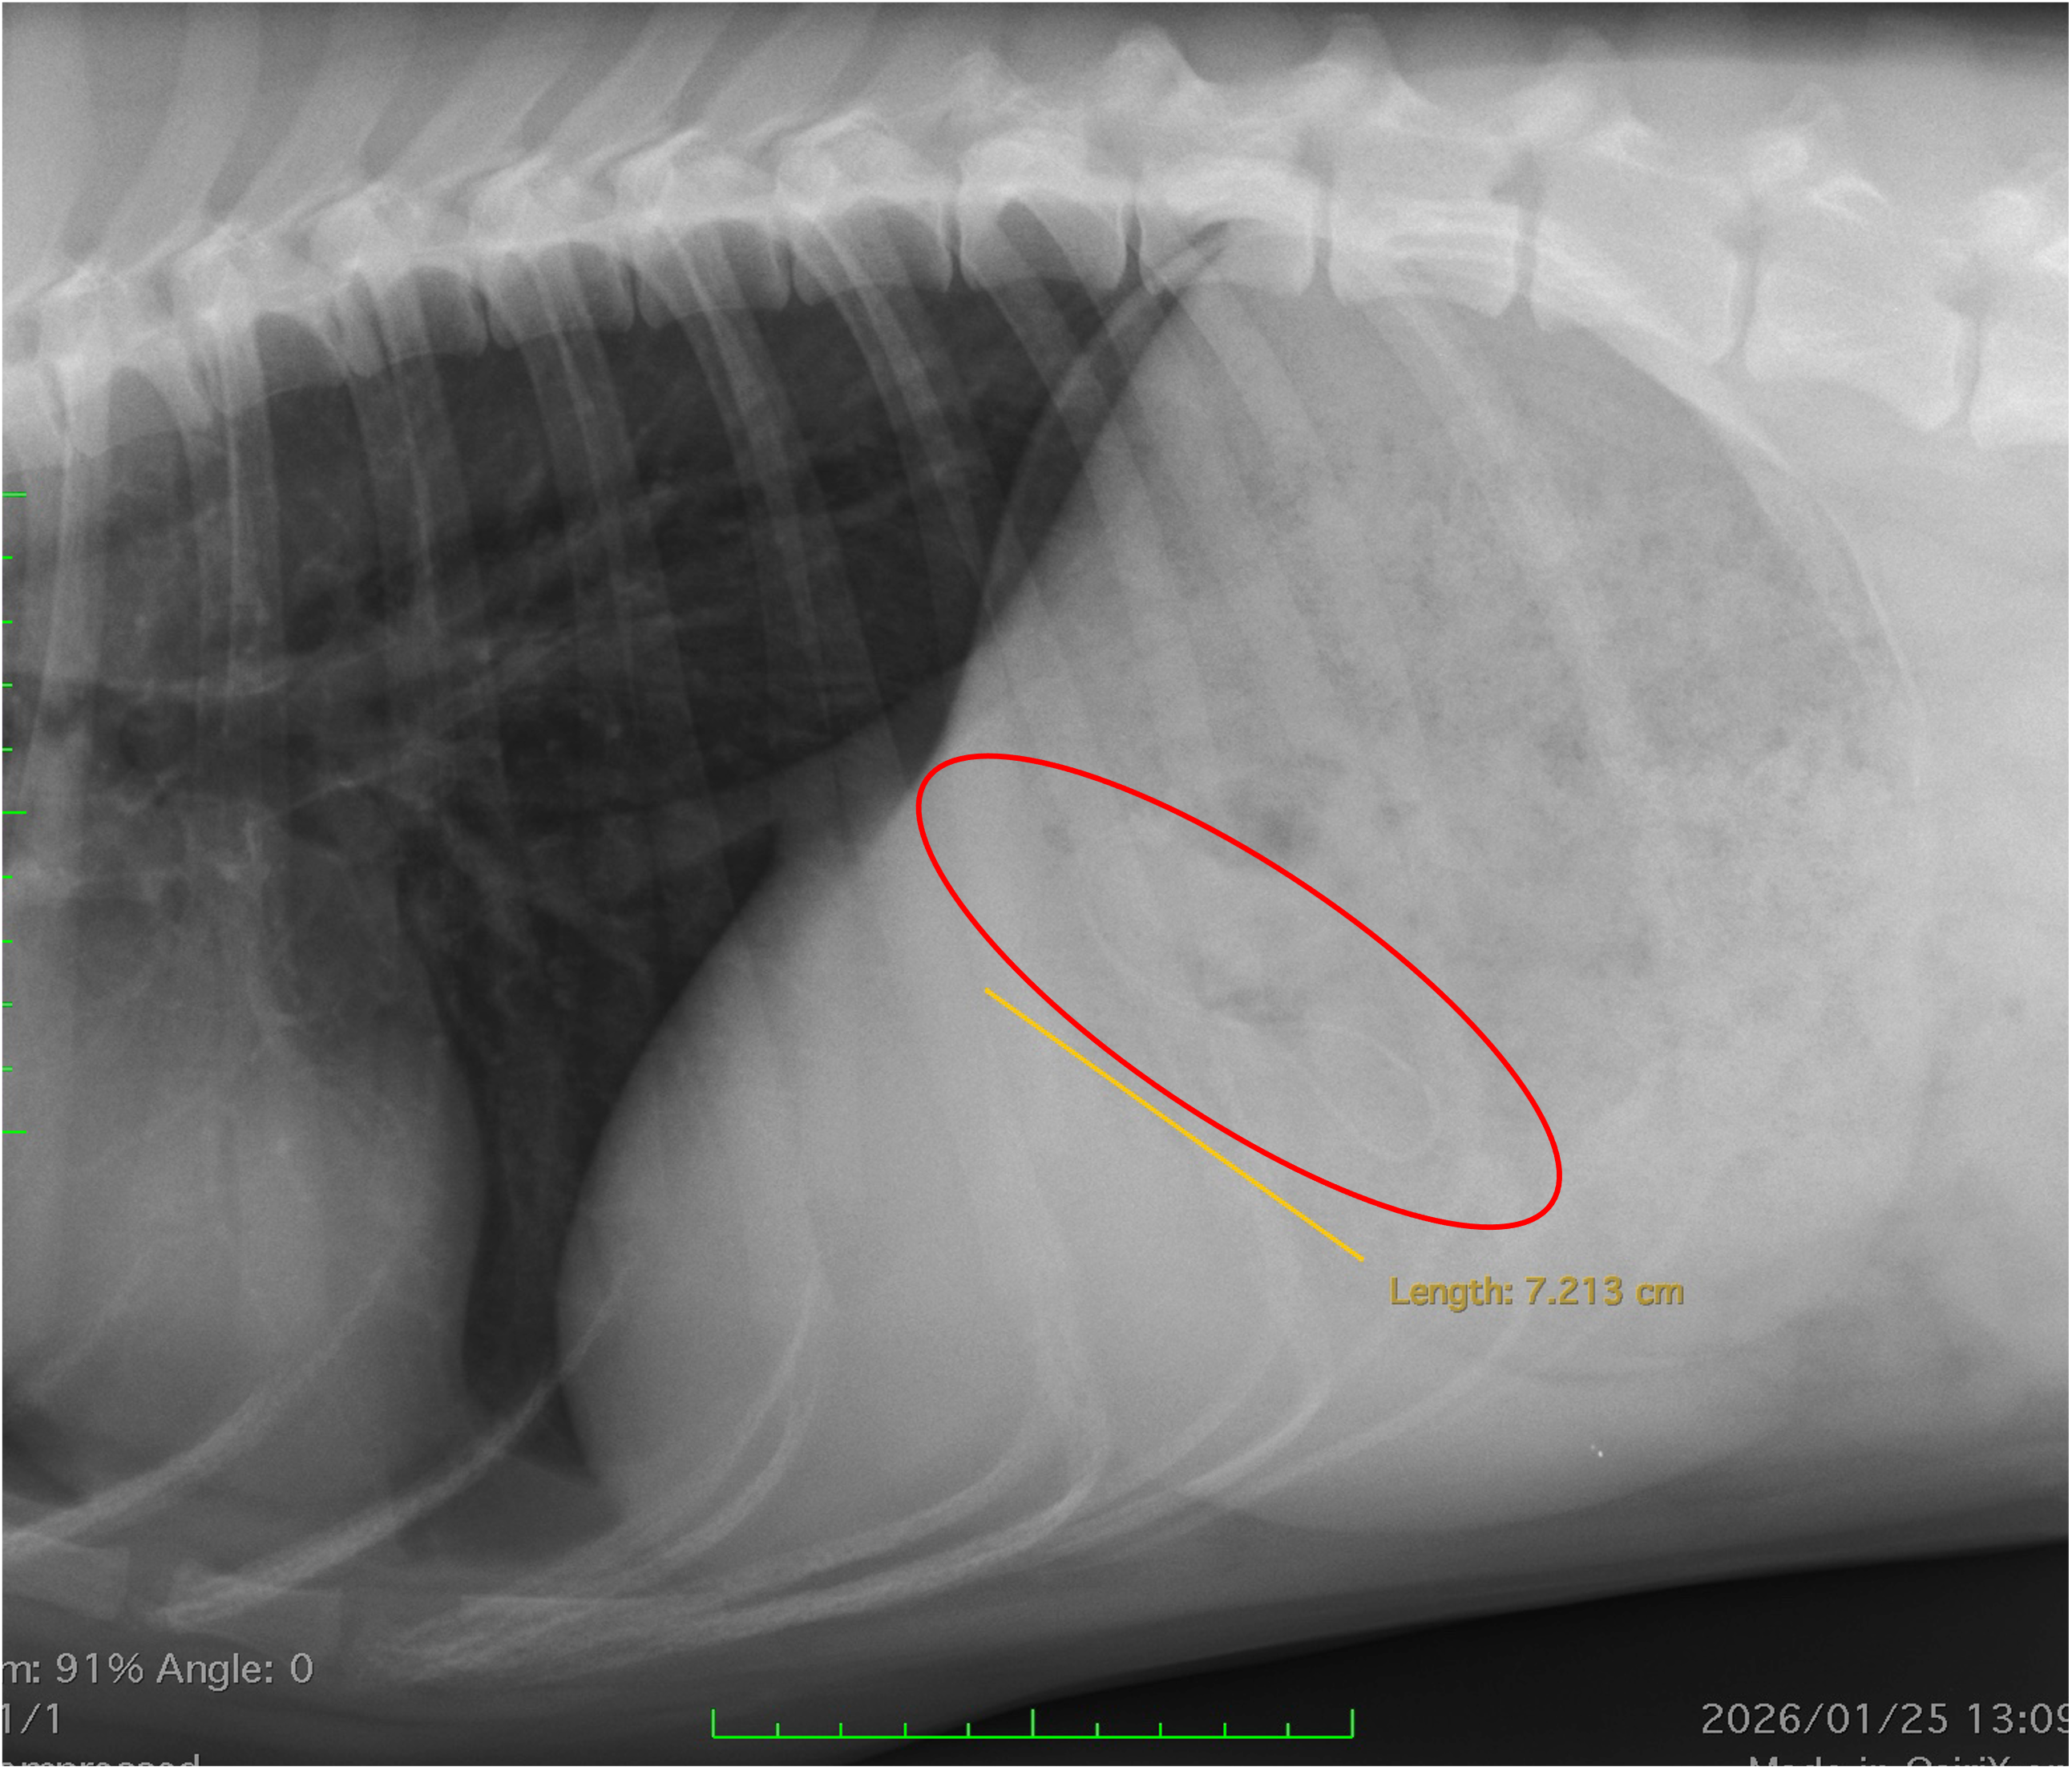

🩻 レントゲン検査で確認

まずレントゲン検査を行ったところ、

胃の中にストラップ状の異物がはっきり確認できました。